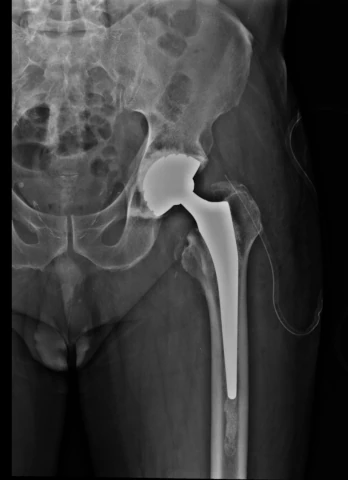

Remplacement de l'articulation coxofémorale par prothèse fémorale cervicocéphalique et cupule mobile

Remplacement de l'articulation coxofémorale par prothèse totale

Remplacement de l'articulation coxofémorale par prothèse totale, avec reconstruction acétabulaire ou fémorale par greffe

Remplacement de l'articulation coxofémorale par prothèse totale, avec renfort métallique acétabulaire